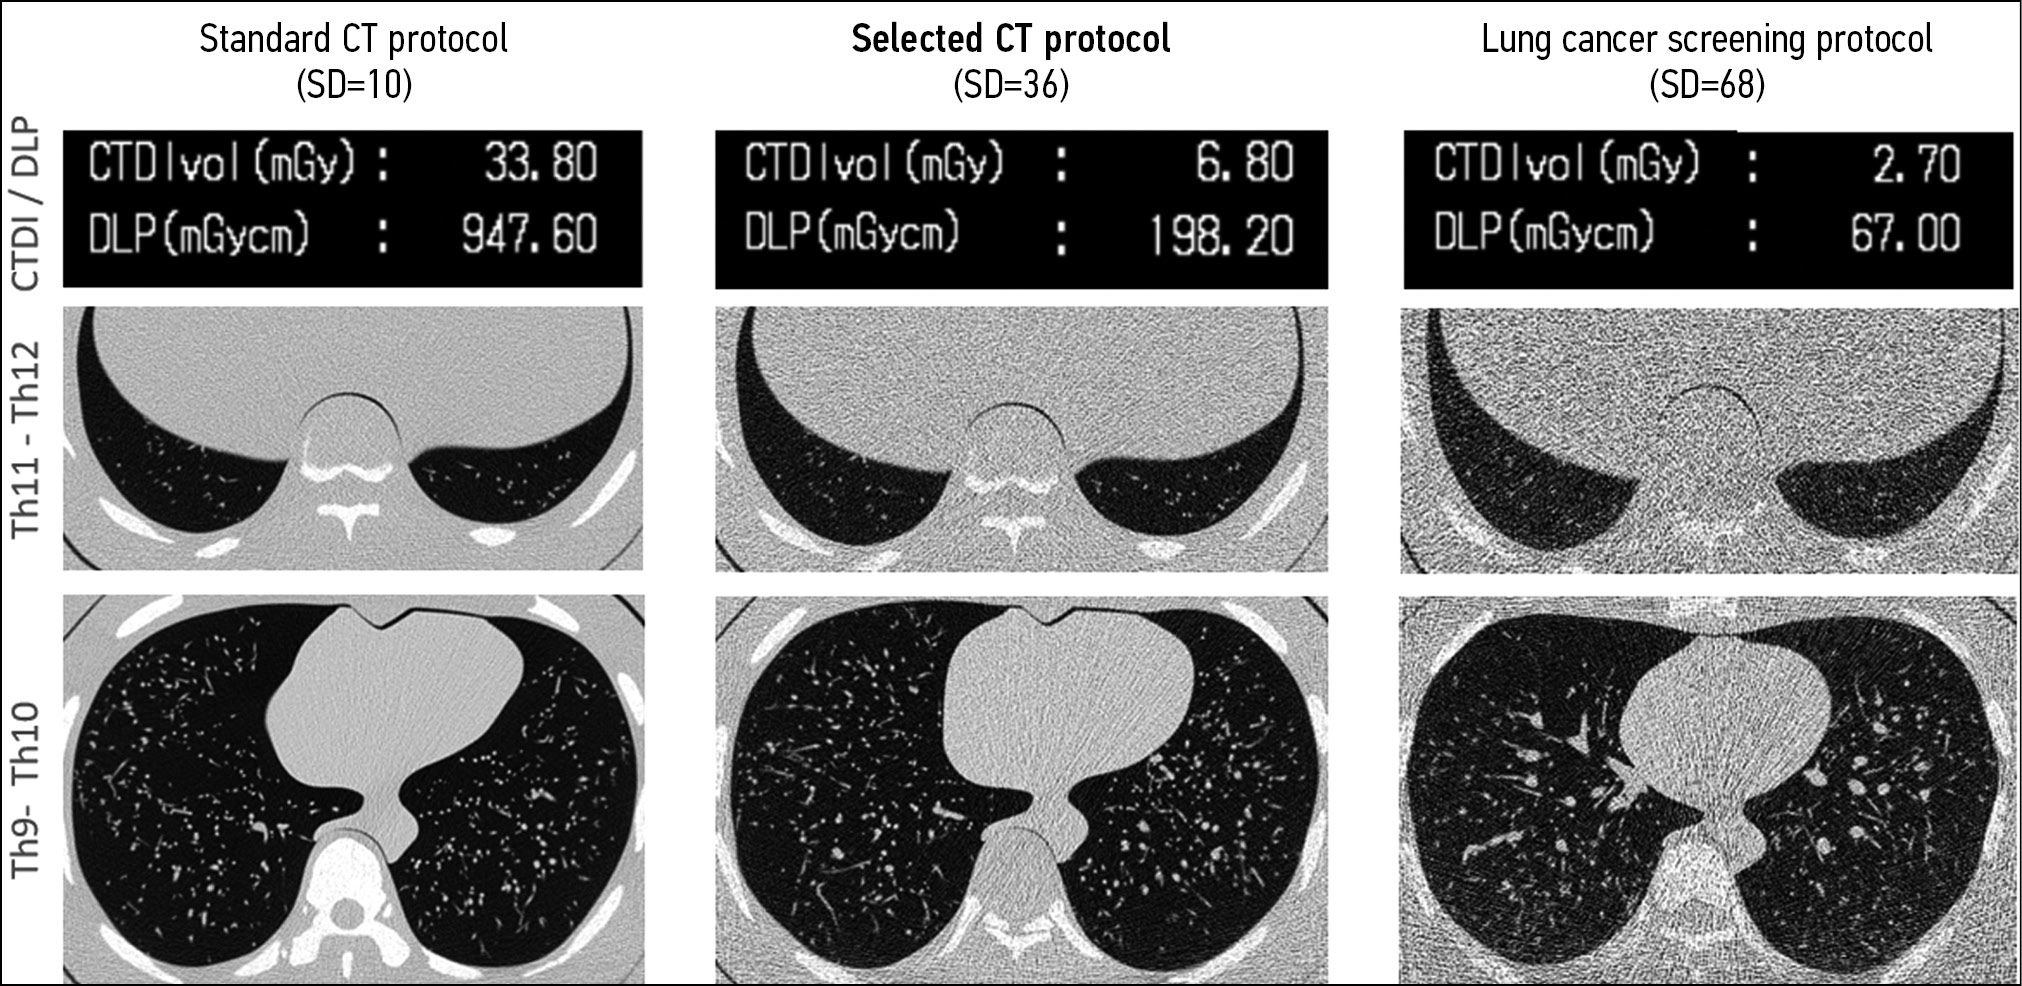

Interestingly, a parameter to be changed when optimizing the scanning protocol can be universal for various clinical tasks. Therefore, in LDCT for lung cancer screening, different groups of authors also changed the tube current [55, 56]. However, the development of a specialized LDCT protocol should be initiated with a study on a model object (phantom) to select the optimal method for reducing the exposure. For example, Gombolevsky et al. [57] developed the LDCT protocol for the diagnosis of COVID-19 using a phantom with thickening plates, while setting the automatic tube current control system (Sure Exposure 3D) to a sufficient level to detect ground-glass lesions with a maximum reduction in radiation exposure (SD = 36). A comparison of the protocol selected according to the results of the phantom study with standard CT and LDCT for lung cancer screening is shown in Fig. 1.

Figure 1. Comparison of a dedicated low-dose computed tomography protocol for COVID-19 (SD = 36) with standard and low-dose computed tomography for lung cancer screening. Data on radiation exposure and axial tomograms of the phantom at the level of the lower and middle zones of the lungs. Low-dose computed tomography for lung cancer screening was developed considering the need for radiation exposure limitation as preventive measures according to SanPin (disease control and prevention standards) and has the lowest signal-to-noise ratio. The proposed protocol for low-dose computed tomography for COVID-19 considers the densitometric characteristics of ground-glass lesions with a significant reduction in radiation exposure.